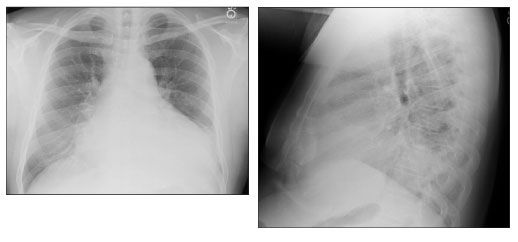

On arrival to the emergency department, S.M. was febrile (temperature, 39.7°C [103.5°F]). He was hemodynamically stable with a room air oxygen saturation of 96%. The physical examination revealed basilar rales on the left with bronchial breath sounds and egophony. The results of the initial laboratory tests included an elevated white blood cell count (14.1 × 109/L, with 86% neutrophils), and hyponatremia (sodium level of 130 mmol/L [normal, 133 - 147]). Results of liver function tests were normal. Chest radiographs and CT scans confirmed a left lower lobe consolidation (Figures 1 and 2). Therapy with piperacillin/tazobactam was started for presumed bacterial pneumonia, and the patient underwent fiberoptic bronchoscopy.

Figure 1. Chest radiographs showing left lower lobe infiltrate. (Images courtesy of the department of radiology, New York-Presbyterian Hospital-Weill Medical College of Cornell University.)